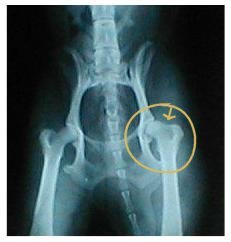

Above are examples of hip x-rays of two different Cavaliers. If

you compare the two you can see that the hip sockets on the

right x-ray are not as deep as those on the left x-ray,

therefore the femoral heads do not sit as deeply into the

sockets—more of the femoral head is left out of the socket.

Also, in the dysplastic x-ray, you can see the circled hip is

much worse than the other hip. The end of the femoral head is

already worn down. Because of stress, the area pointed to behind

the femoral head has filled in so much the indentation is nearly

gone. Compare this to the other three hips that have good

indentation behind the femoral head. NOTE: the dog with the

dysplastic hips showed NO signs of hip dysplasia when walking

or running. The x-ray was taken only because the owner wanted to

make sure the dog did not have hip dysplasia before it was bred.

Since the dog does have hip dysplasia, the breeder decided not

to breed the dog. Also, BOTH parents are OFA clear of hip

dysplasia, and so is the one other sibling whose hips have been

x-rayed and sent to OFA.